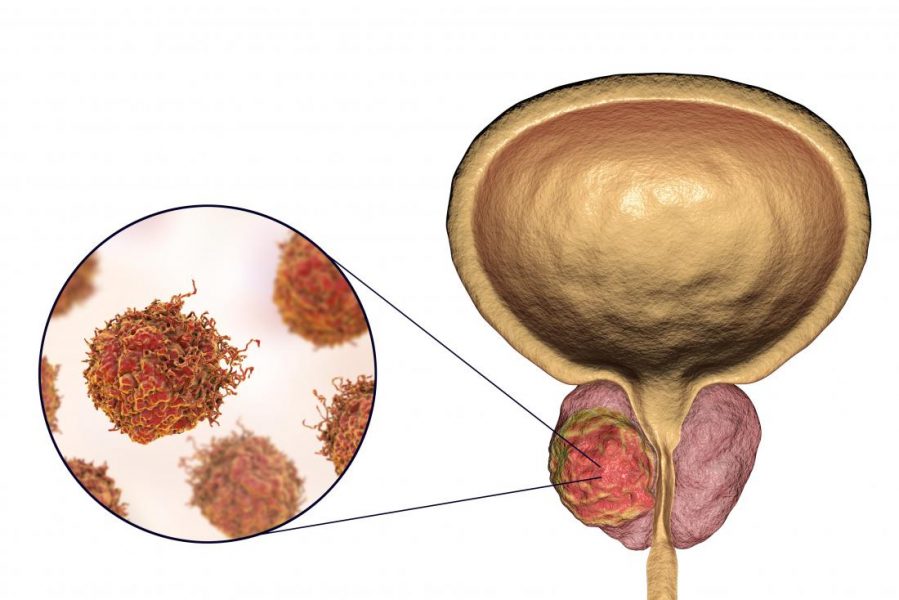

انواع غربالگری سرطانها

انواع غربالگری سرطانها شامل روشهایی است که با بکارگیری آنها پزشکان نشانههای اولیه سرطان را در افرادی که هیچ علامتی از ابتلا به آن ندارند جستجو میکنند. هدف از انجام انواع غربالگری سرطانها کشف مراحل اولیه سرطان قبل از داشتن فرصت رشد و انتشار تومور است. کنسرهای کشف شده از طریق غربالگری اغلب کوچک و […]